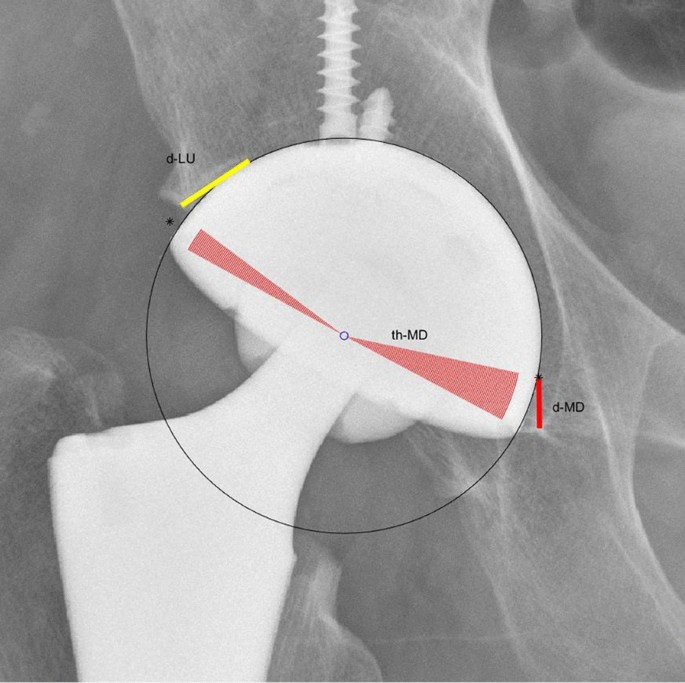

The significance of several variables was defined as shown in Table 5. (Fig. 7).

Table 5 Some variables used in this study and their significance

Some variables and their significance

median_d_MD = 8.01 mm, median_d_LU = 8.17 mm, median_th_MD = 17.5°, median_cupsize = 52 mm. (Table 5).

On the AP X-ray of the pelvis, A is the lateral superior intersection of the cup and the inner wall of the acetabulum. The distance between it and the lateral edge of the acetabulum is d_LU. By measuring the d_LU on postsurgery X-ray of all 406 cases, the median of d_LU is obtained. When templating a new preoperative AP X-ray of the pelvis, as long as we know the coordinates of the lateral edge of the acetabulum and the contour of the nearby acetabular edge, combining with the value of median_d_LU, the ideal position of A can be estimated (A is located on this contour and its distance from the lateral edge of the acetabulum is median_d_LU). In a similar way, the ideal position of B, the medial inferior intersection of the cup and the inner wall of the acetabulum, can also be obtained.

By measuring the th_MD on postsurgery X-ray of all 406 cases, the median of this angle can be obtained (median_d_MD); the lateral uncoverage should not exceed 20%. It can be known that the average coverage ratio is 10%, then the ideal angle on the lateral side should be 180° × 10% = 18°, so the ideal ∠AOB should be equal to 180° − (18 + median_d_MD).

In this way, A, B and ∠AOB are obtained, and then the position and radius of the cup can be calculated.